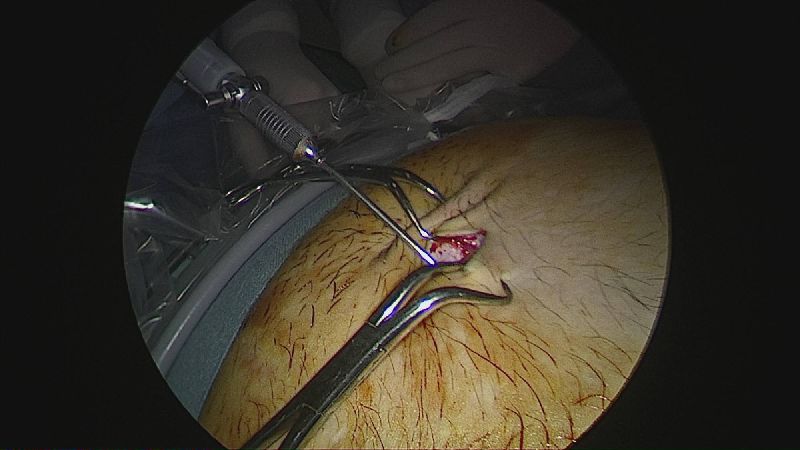

Operația ”de micșorare a stomacului” se realizează miniminvaziv (laparoscopic) și constă în îndepărtarea marii curburi gastrice cu păstrarea antrului gastric și a micii curburi sub forma unui tub calibrat pe o sondă.

Tehnica aduce beneficiile chirurgiei laparoscopice, durere redusă, externare în primele 48 ore de la intervenție. Avantajul său constă în confortul oferit pacientului care prezintă senzația de sațietate rapid prin umplerea unui stomac de doar 100 ml, reducerea senzației de foame prin suprimarea secreției de grelina. De asemenea, nu modifică traseul alimentelor, nu exclude segmente digestive din circuit și pierderea excesului ponderal poate ajunge până la 100%.